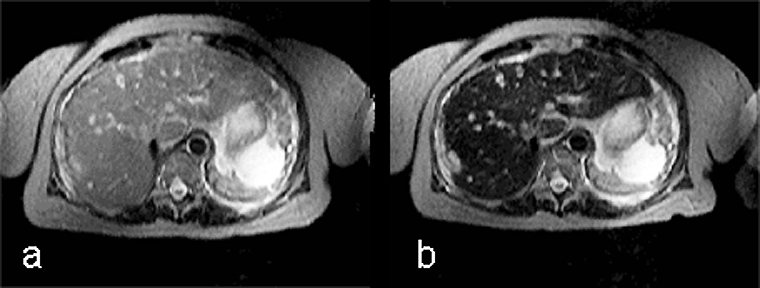

Ferumoxides, or super-paramagnetic iron oxides, are negative enhancers taken up by the normal liver, which contains reticuloendothelial cells, but not by lesions that lack reticuloendothelial cells (Figure 13-15) [⇒ Paley; cf. iron oxides].

Figura 13-15:

Example of a negative liver contrast agent (ferumoxide). This particulate agent is taken up by en­do­the­lial and Kupffer's cells. They darken the liver tissue due to their effective shortening of the T2 relaxation time.

T2-weighted GRE: (a) precontrast; (b) postcontrast. The liver metastases are well delineated on the post-contrast image; with this agent, the normal liver tissue becomes black.